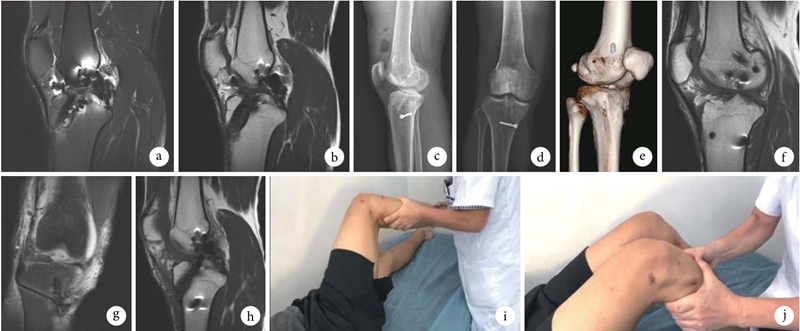

图4 患者,男,44岁,右膝关节ACL初次重建术后5年行翻修术,合并骨隧道扩大 a、b.术前MRI矢状位;c.术后2d侧位X线片;d.术后2d正位X线片;e.术后3d CT三维重建;f.术后1周MRI矢状位显示各骨隧道点位;g.术后1周MRI冠状位显示ALL骨隧道位置;h.术后2年MRI矢状位显示移植物情况良好;i、j.术后2年患者右膝关节功能,轴移试验0级,Lachman试验Ⅰ度松弛,活动范围0°~140°